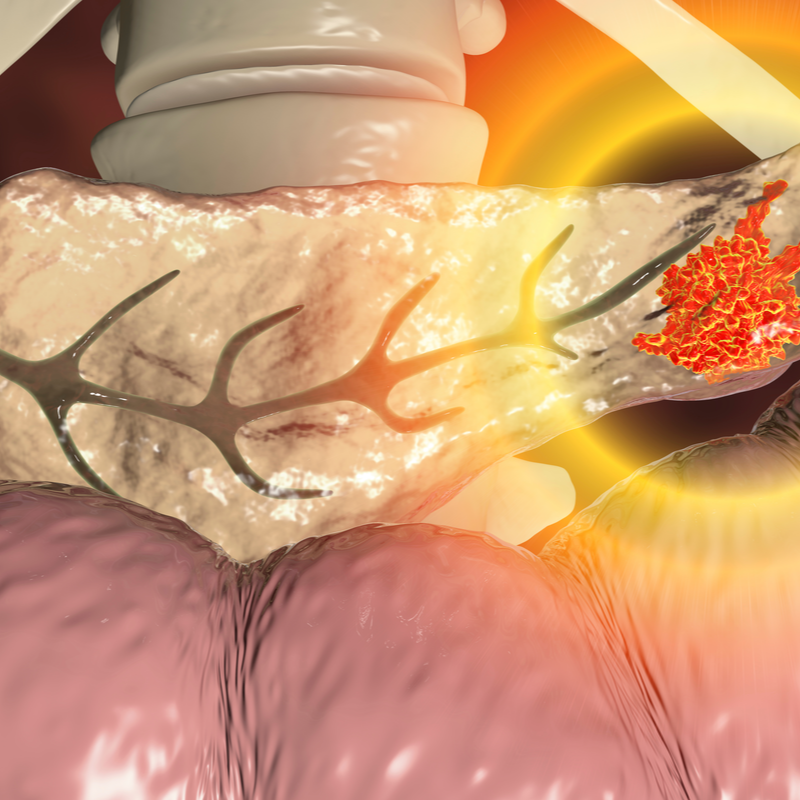

Kaulu vēzis